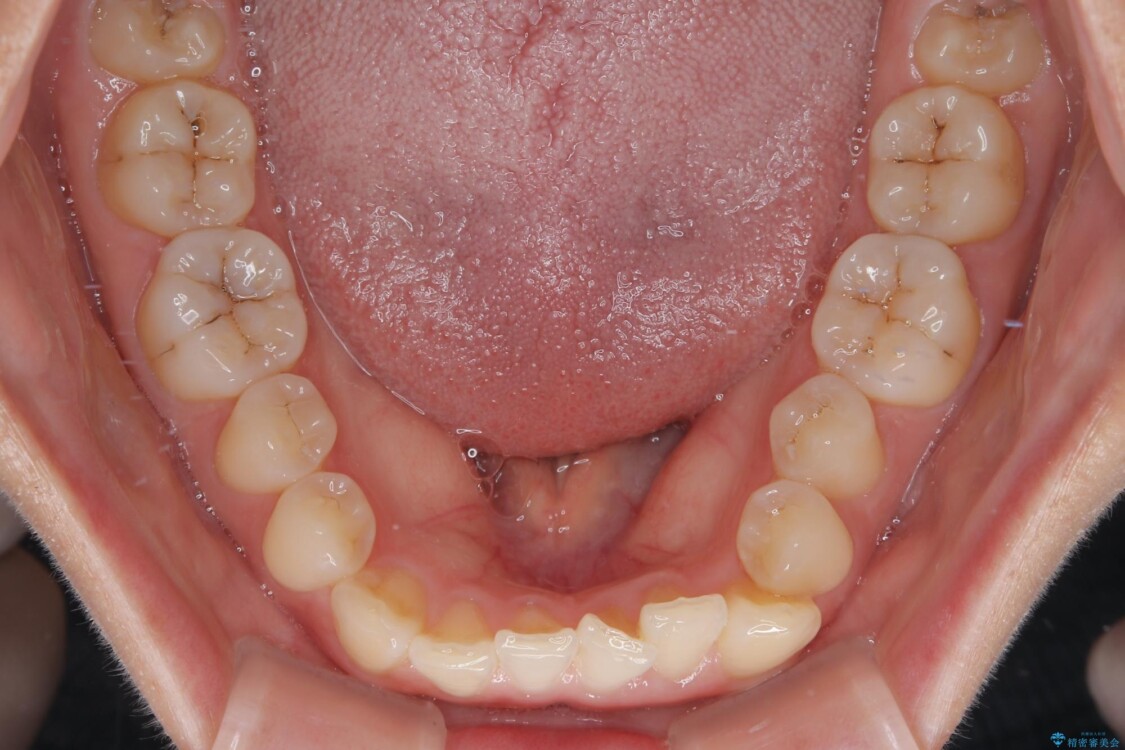

診察の結果、上下の前歯部に**叢生(そうせい/歯のガタガタ・重なり)**が認められました。

特に上の前歯にはねじれや重なりがあり、審美的にも清掃性にも影響している状態でした。

治療前

• 前歯のねじれ・ガタガタを10か月で改善!20代女性の矯正治療|クリアブラケットでむし歯になりにくい歯並びへ改善 治療前画像